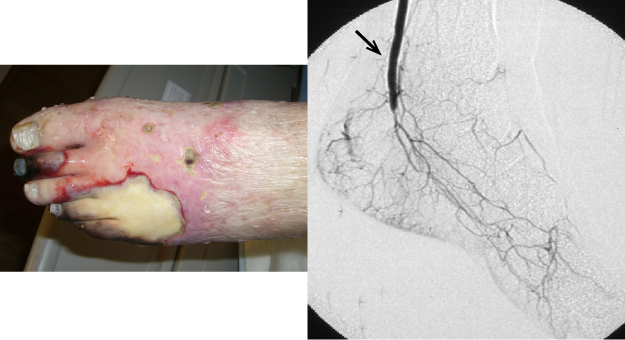

図1. 全身型強皮症

42才/女性

右膝下動脈閉塞による足趾壊疽右総足底動脈バイパス(矢印:吻合部)により下肢救済